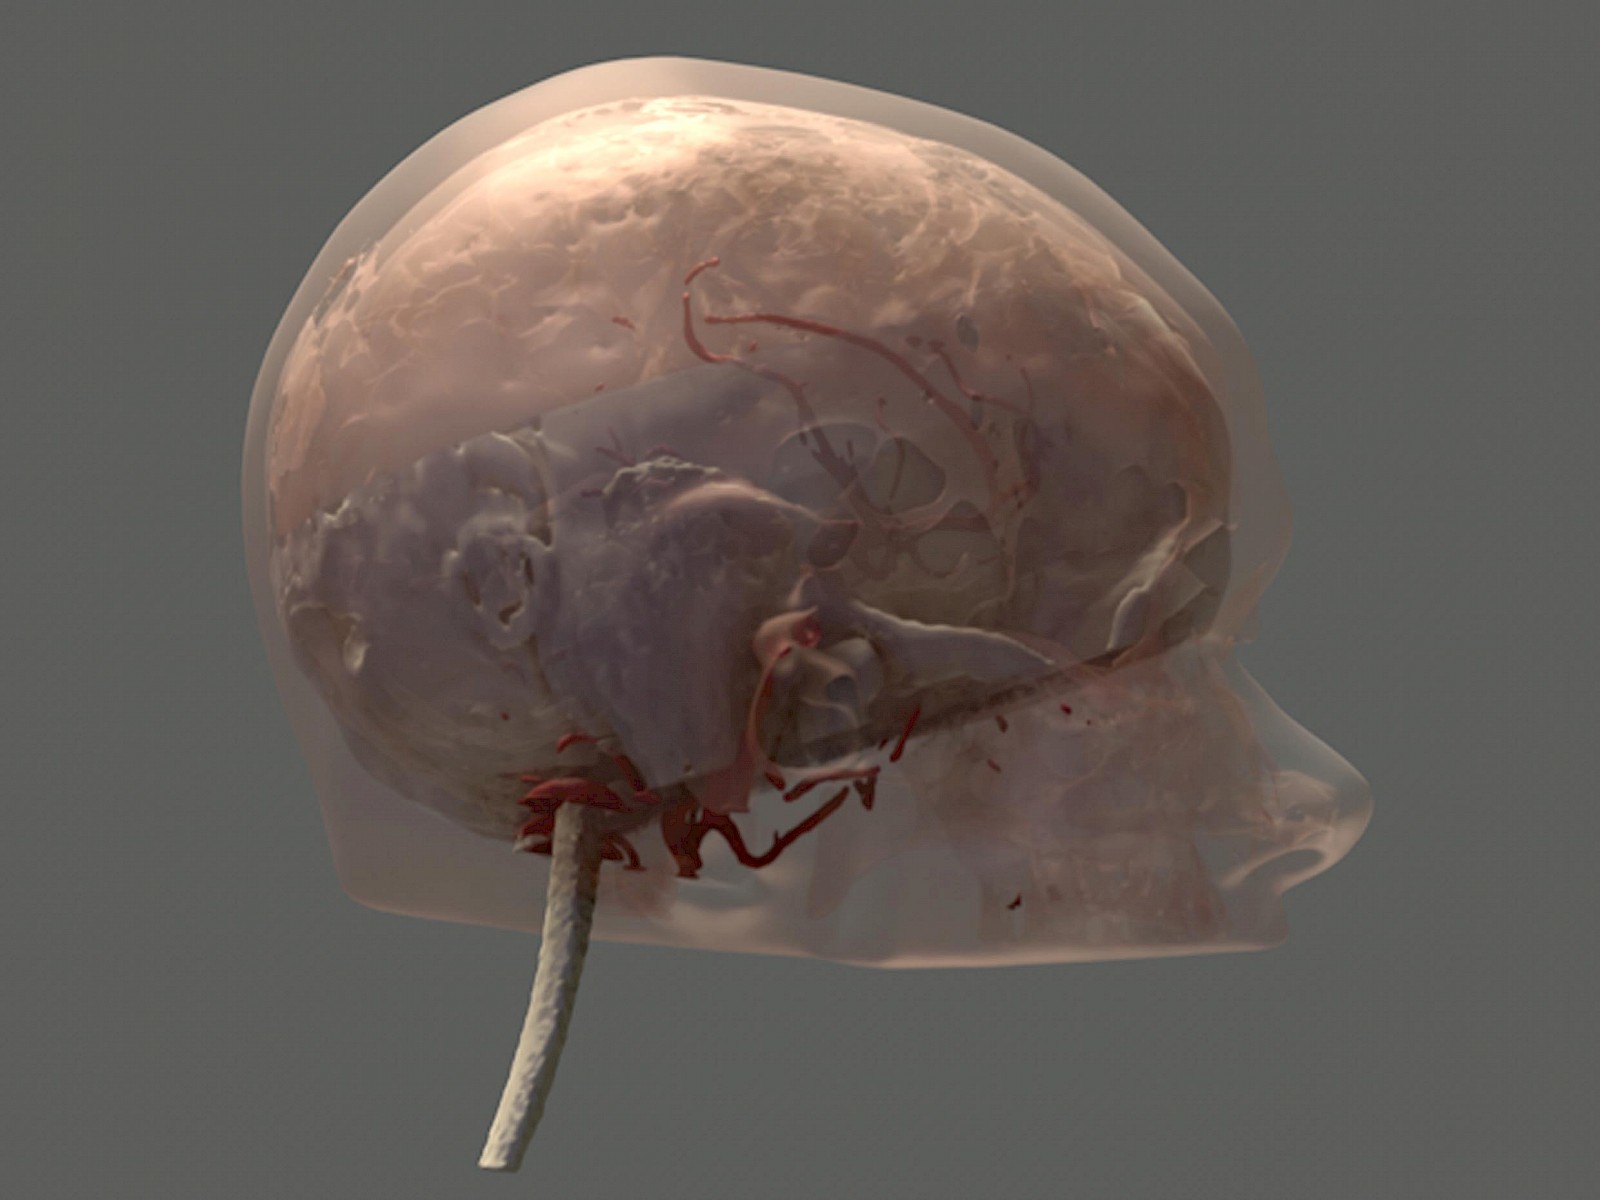

Entwickelt und geforscht wird von mir an digitalen 3D-Modellen des Hirnstamms und dessen umliegenden Strukturen. Diese sind interaktiv nutzbar und ab Herbst von Chirurgen als individuelle Patientendaten über eine OP-Navigations-Applikation einsetzbar.

Die dreidimensionalen Hirn-Strukturen werden über den gezielten Einsatz verschiedener Medien entwickelt, basierend auf den bildgebenden Verfahren MRT und CT. Die MRT-Datensätze besitzen ein bestimmtes Format, das nicht direkt bearbeitbar ist. Diese Daten verarbeite ich anfangs selektiv, erst nach diesem Prozess sind diese direkt gestaltbar. Die 3D-OP-Situs Prototyp-Applikation unterstützt die präoperative Planung und leistet Wissensvermittlung an Fachpersonal. Dies erweitert das Sichtfeld während der Operation und das räumliche Verständnis des Chirurgen. Die medizinischen Daten und der OP-Situs werden interaktiv erfahrbar. Dieser Prozess lässt die abstrakten medizinischen Daten im Raum und in Farbe erscheinen.